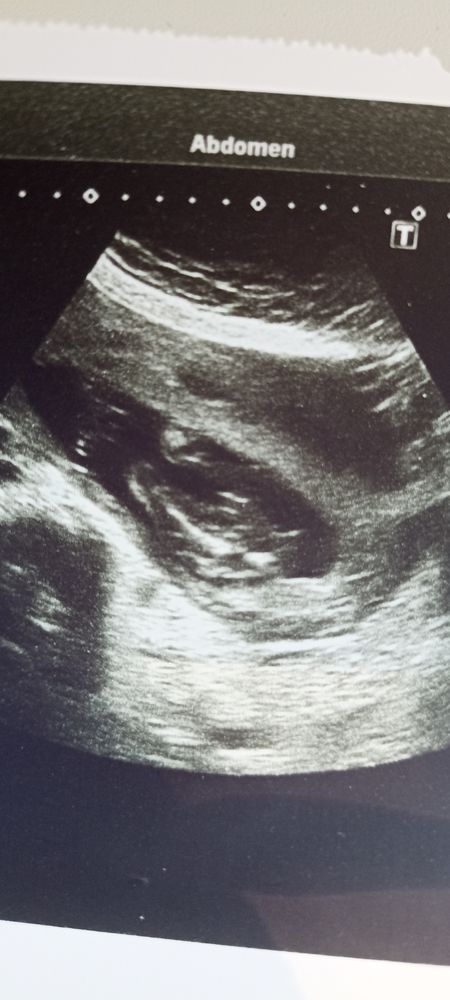

Мальчик или девочка ? Фото узи

На девочку как будто похоже. Если кому-то на 1 скрининге смотрели не по бугорку, а развернув продольно с попы - откликнитесь, подтвердился пол и как там торчит у всех... мне с попы смотрели пол, сказали мальчик, прямо шпулька такая заметная была, но сомнения.

Девочка ))

Будем надеяться, что мальчик. Носик для него подходящий 😊

Думаю, мальчик.

23.04.2022

Мне кажется мальчик

Изображение Мне кажется девочка) у меня есть такое фото, бугорок такой же "лежачий")) но не известно кто, жду 2 скрининг Хочется очень девочку)

По мне, девочка 👧

Похоже на девочку